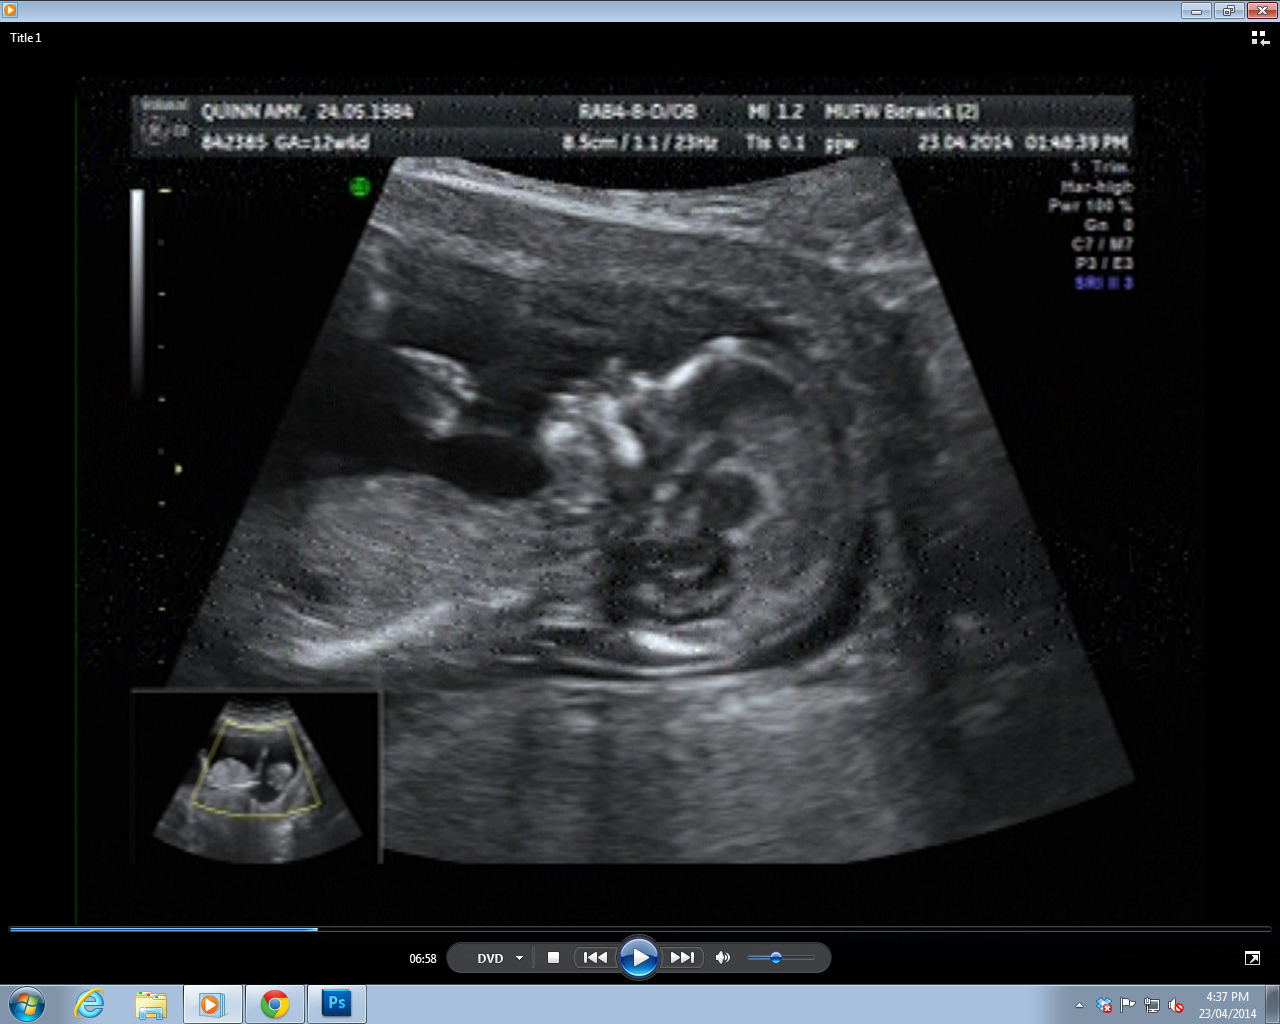

Three nub shots I was able to get, pulled off the DVD. I really didn't have much to work with - in 30 minutes of footage, these were the ONLY clear(ish) nub shots the whole time.

Attachment 18363Attachment 18364Attachment 18365